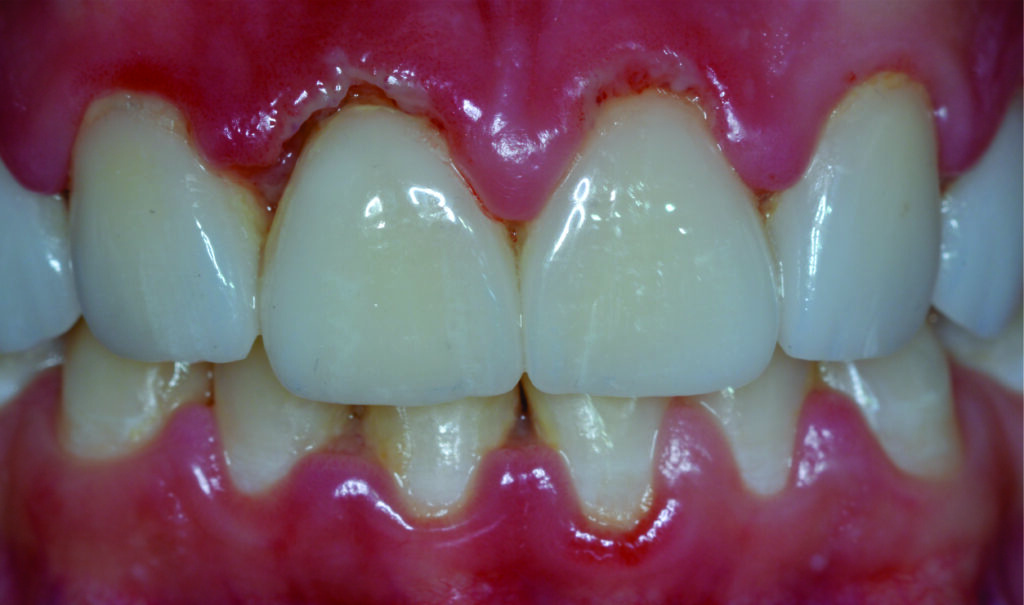

A gengivite é caracterizada pela inflamação do tecido gengival, causada pela proliferação de bactérias. Quando a higiene bucal não é feita da forma adequada ocorre o acúmulo de bactérias que leva a formação de uma placa bacteriana, uma película viscosa e incolor. Em um primeiro momento, esta placa é de fácil remoção, com o passar do tempo ela se calcifica e adere firmemente ao dente (Tártaro). Caso não seja removida, essa placa pode liberar toxinas que afetam a gengiva e desencadeiam o problema.

Inflamação

Gengiva inflamada;

Vermelha escura;

Inchada;

Dolorida;

Sangramento e até supuração ao toque;

Pode haver Mau Hálito;

NÃO há Perda Óssea.